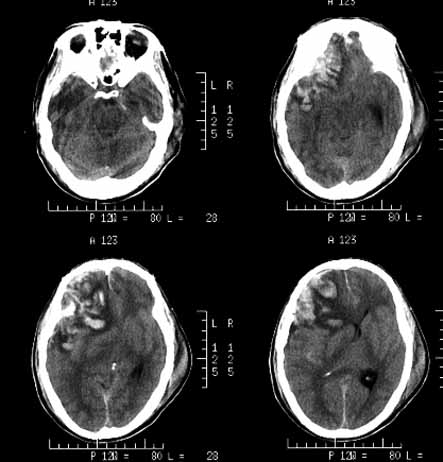

Bkm6f.jpg

(443 × 462像素,文件大小:31 KB,MIME类型:

脑挫裂伤